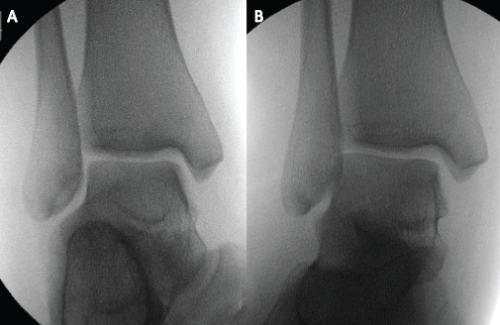

She was examined under general anesthesia. Screening from an imaging intensifier did not show the medial clear space increase more than 4 mm while external rotation of her foot was enforced (Figure 7). Therefore, we diagnosed her syndesmosis is stable. Subsequently, a shot leg plaster was applied for six weeks. She was reviewed in clinic in one-year post-injury, and was pain-free.

Figure 7: Intra-operative imaging intensifier screening showed that there was no significant medial clear space increase on external stress view (b) compared with non stress AP view (a).